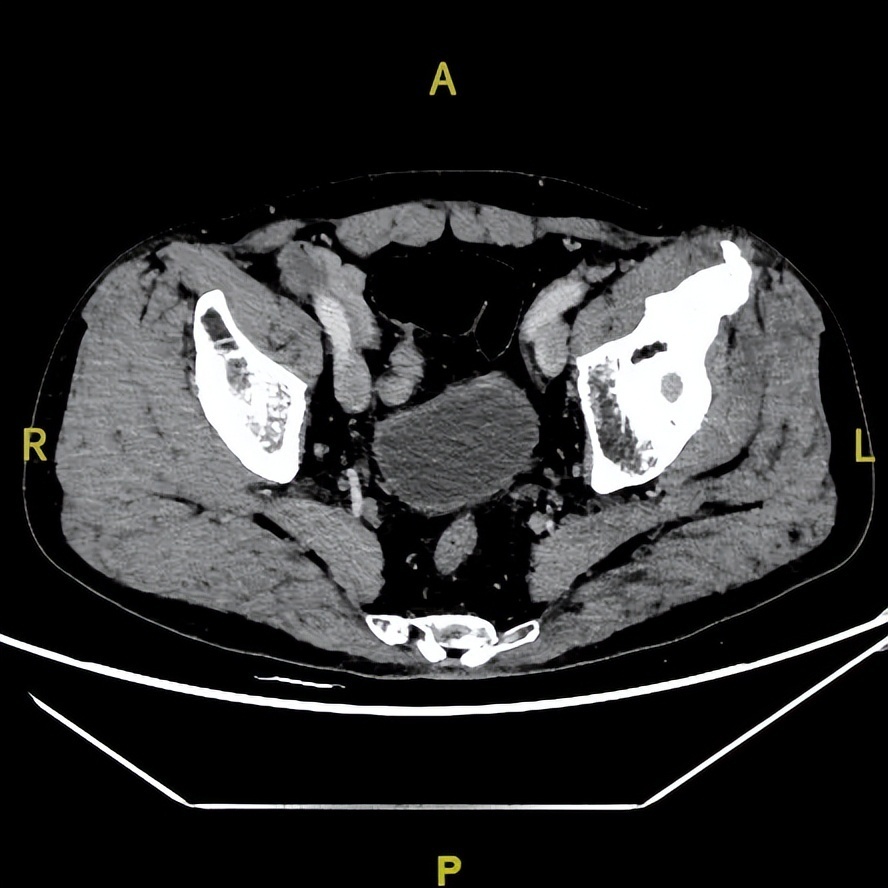

2023年1月31日

2024年2月19日

2025年9月24日

△治疗后不同随访时间的胸部及髋关节CT病灶变化